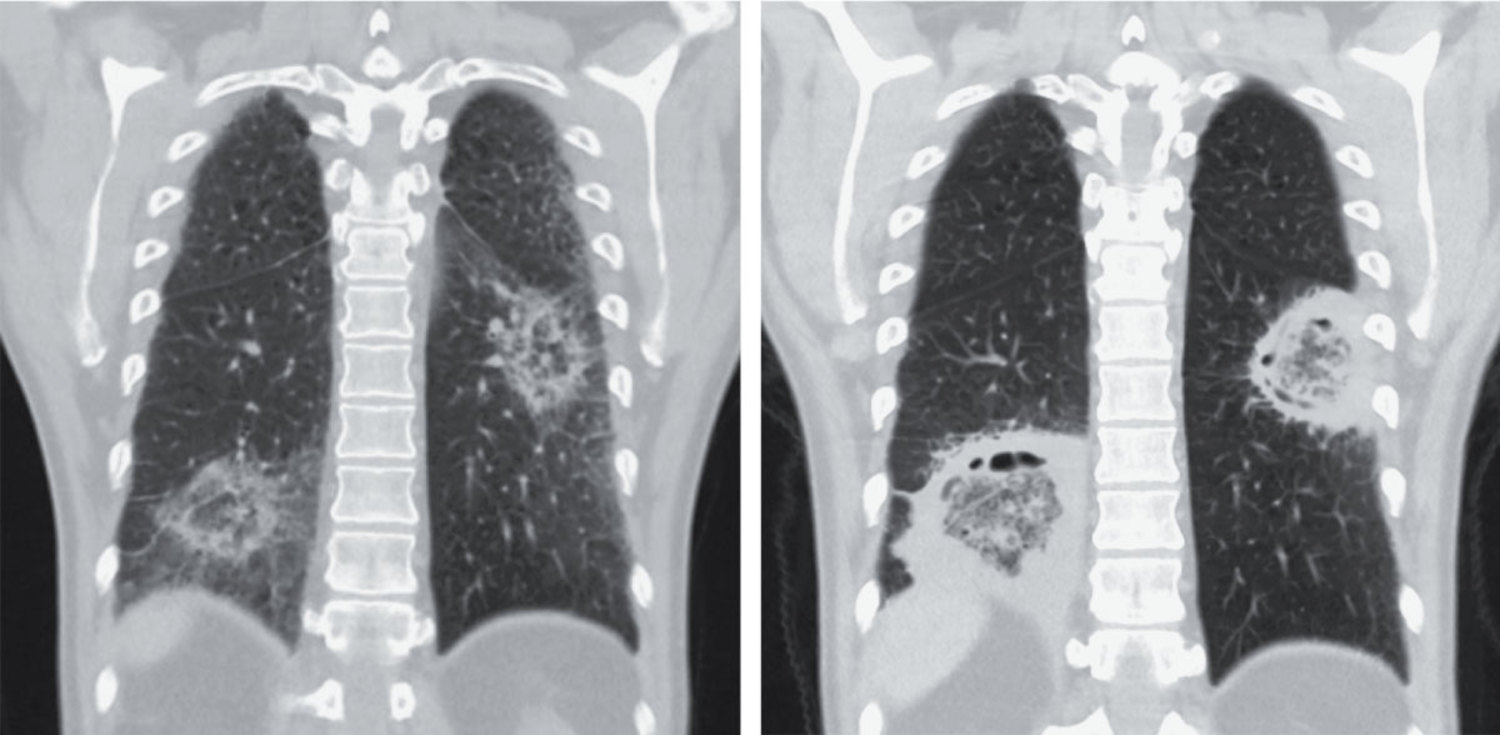

A 49-year-old man with acute myeloid leukemia who had been admitted to the hospital for induction chemotherapy was evaluated for prolonged neutropenic fever. On physical examination, crackles were identified at the lung bases. Computed tomography of the chest is shown. Empiric treatment with amphotericin B was started. After 2 weeks of treatment, repeat CT of the chest is shown. What is the most likely diagnosis?

胸部CT显示圆形实变影,中心呈磨玻璃样密度,周围环绕环形实变,这种表现称为反晕征(reversed halo sign),可见于侵袭性真菌感染。随即开始给予两性霉素B经验性治疗,但因中性粒细胞恢复,复查CT时病灶反而加重。最终通过对切除肺组织的病理学检查和PCR检测肺组织标本,确认病原体为微小根毛霉(Rhizomucor pusillus),因此诊断为肺毛霉病(Pulmonary mucormycosis)。